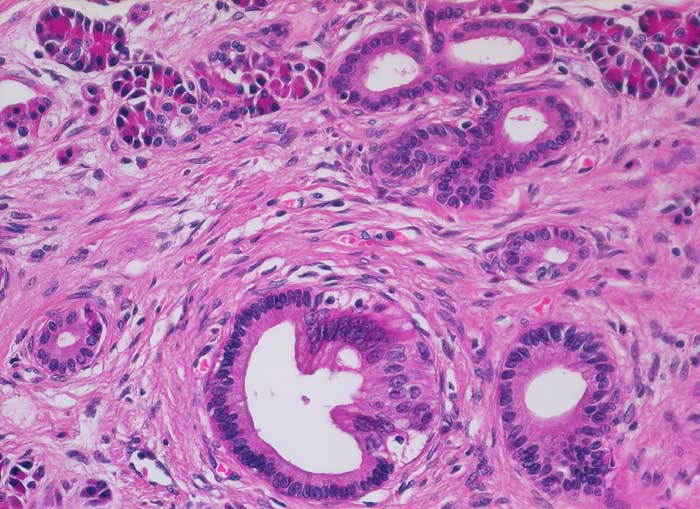

Im Gegensatz zum duktalen Adenokarzinom ist das erhaltene Parenchym bei der chronischen Pankreatitis lobulär angeordnet. Drüsenepithelien zeigen keine Atypien. Karzinomverdächtig sind irregulär infiltrierende atypische Drüsen, atypische Drüsen in unmittelbarer Nachbarschaft von grösseren Gefässen ohne dazwischenliegende Azini, Perineuralscheideninvasion, rupturierte oder inkomplette Drüsen, und Drüsen mit luminalem nekrotischem Detritus.